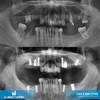

السن المطمور - ماذا يعني السن المطمور؟ يُطلق على الأسنان التي لم تستطع أخذ مكانها في الفم بالرغم من حلول وقت بزوغها لعدة أسباب مختلفة "الأسنان المطمورة". الأضراس الثالثة الكبيرة (المعروفة أيضاً بأسنان العقل أو أضراس العشرين)، هي أكثر الأسنان المطمورة شيوعاً.

الأسنان المطمورة